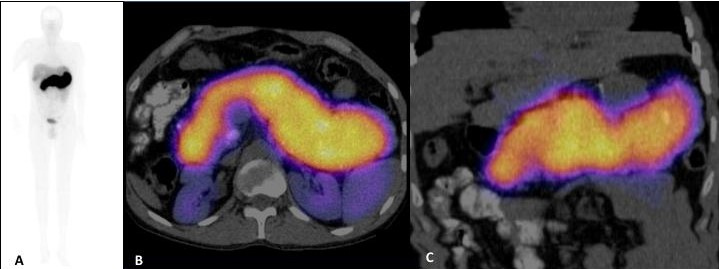

Se realiza gamagrafía con 99mTc-HYNIC-Octreotido y SPECT-CT de abdomen superior que mostró sobreexpresión de receptores de somatostatina en todo el parénquima pancreático, compatible con tumor neuroendócrino (Fig. 3). La endoscopía documentó várices fúndicas GOV 1 de Sarin y cambios por aplicación de cianocrilato y esclerosante en fondo y cuerpo gástrico. Por ultrasonido endoscópico se toman biopsias de cabeza, cuerpo y cola pancreática con diagnóstico de infiltración generalizada del páncreas por tumor neuroendócrino bien diferenciado, G1, Cromogranina (+), sinaptofisina (+) y Ki67<1%. Niveles de insulina, somatostatina y VIP negativos (Fig. 4).